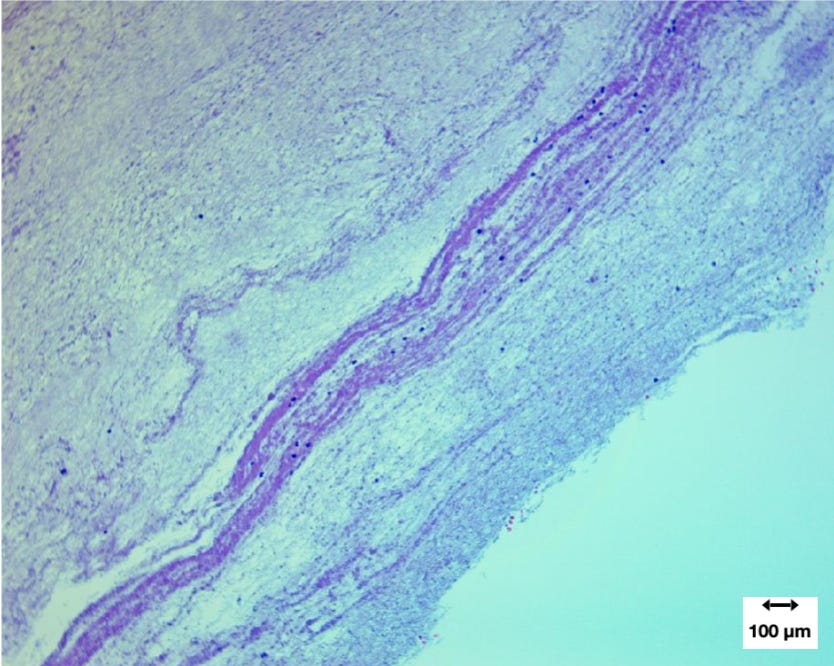

At higher magnification, the fibrin architecture became more apparent. Researchers observed tightly interwoven fibrin strands forming dense networks within the casts.

Distorted leukocytes were occasionally embedded within this matrix. Many of these cells showed signs of membrane rupture and nuclear extrusion.

Interestingly, intact red blood cells were largely absent. Instead, streaks of hemoglobin suggested that erythrocytes had broken down within the structure.

In some regions, fibrin fibers formed banded structures resembling partial Lines of Zahn, although these laminations were incomplete.